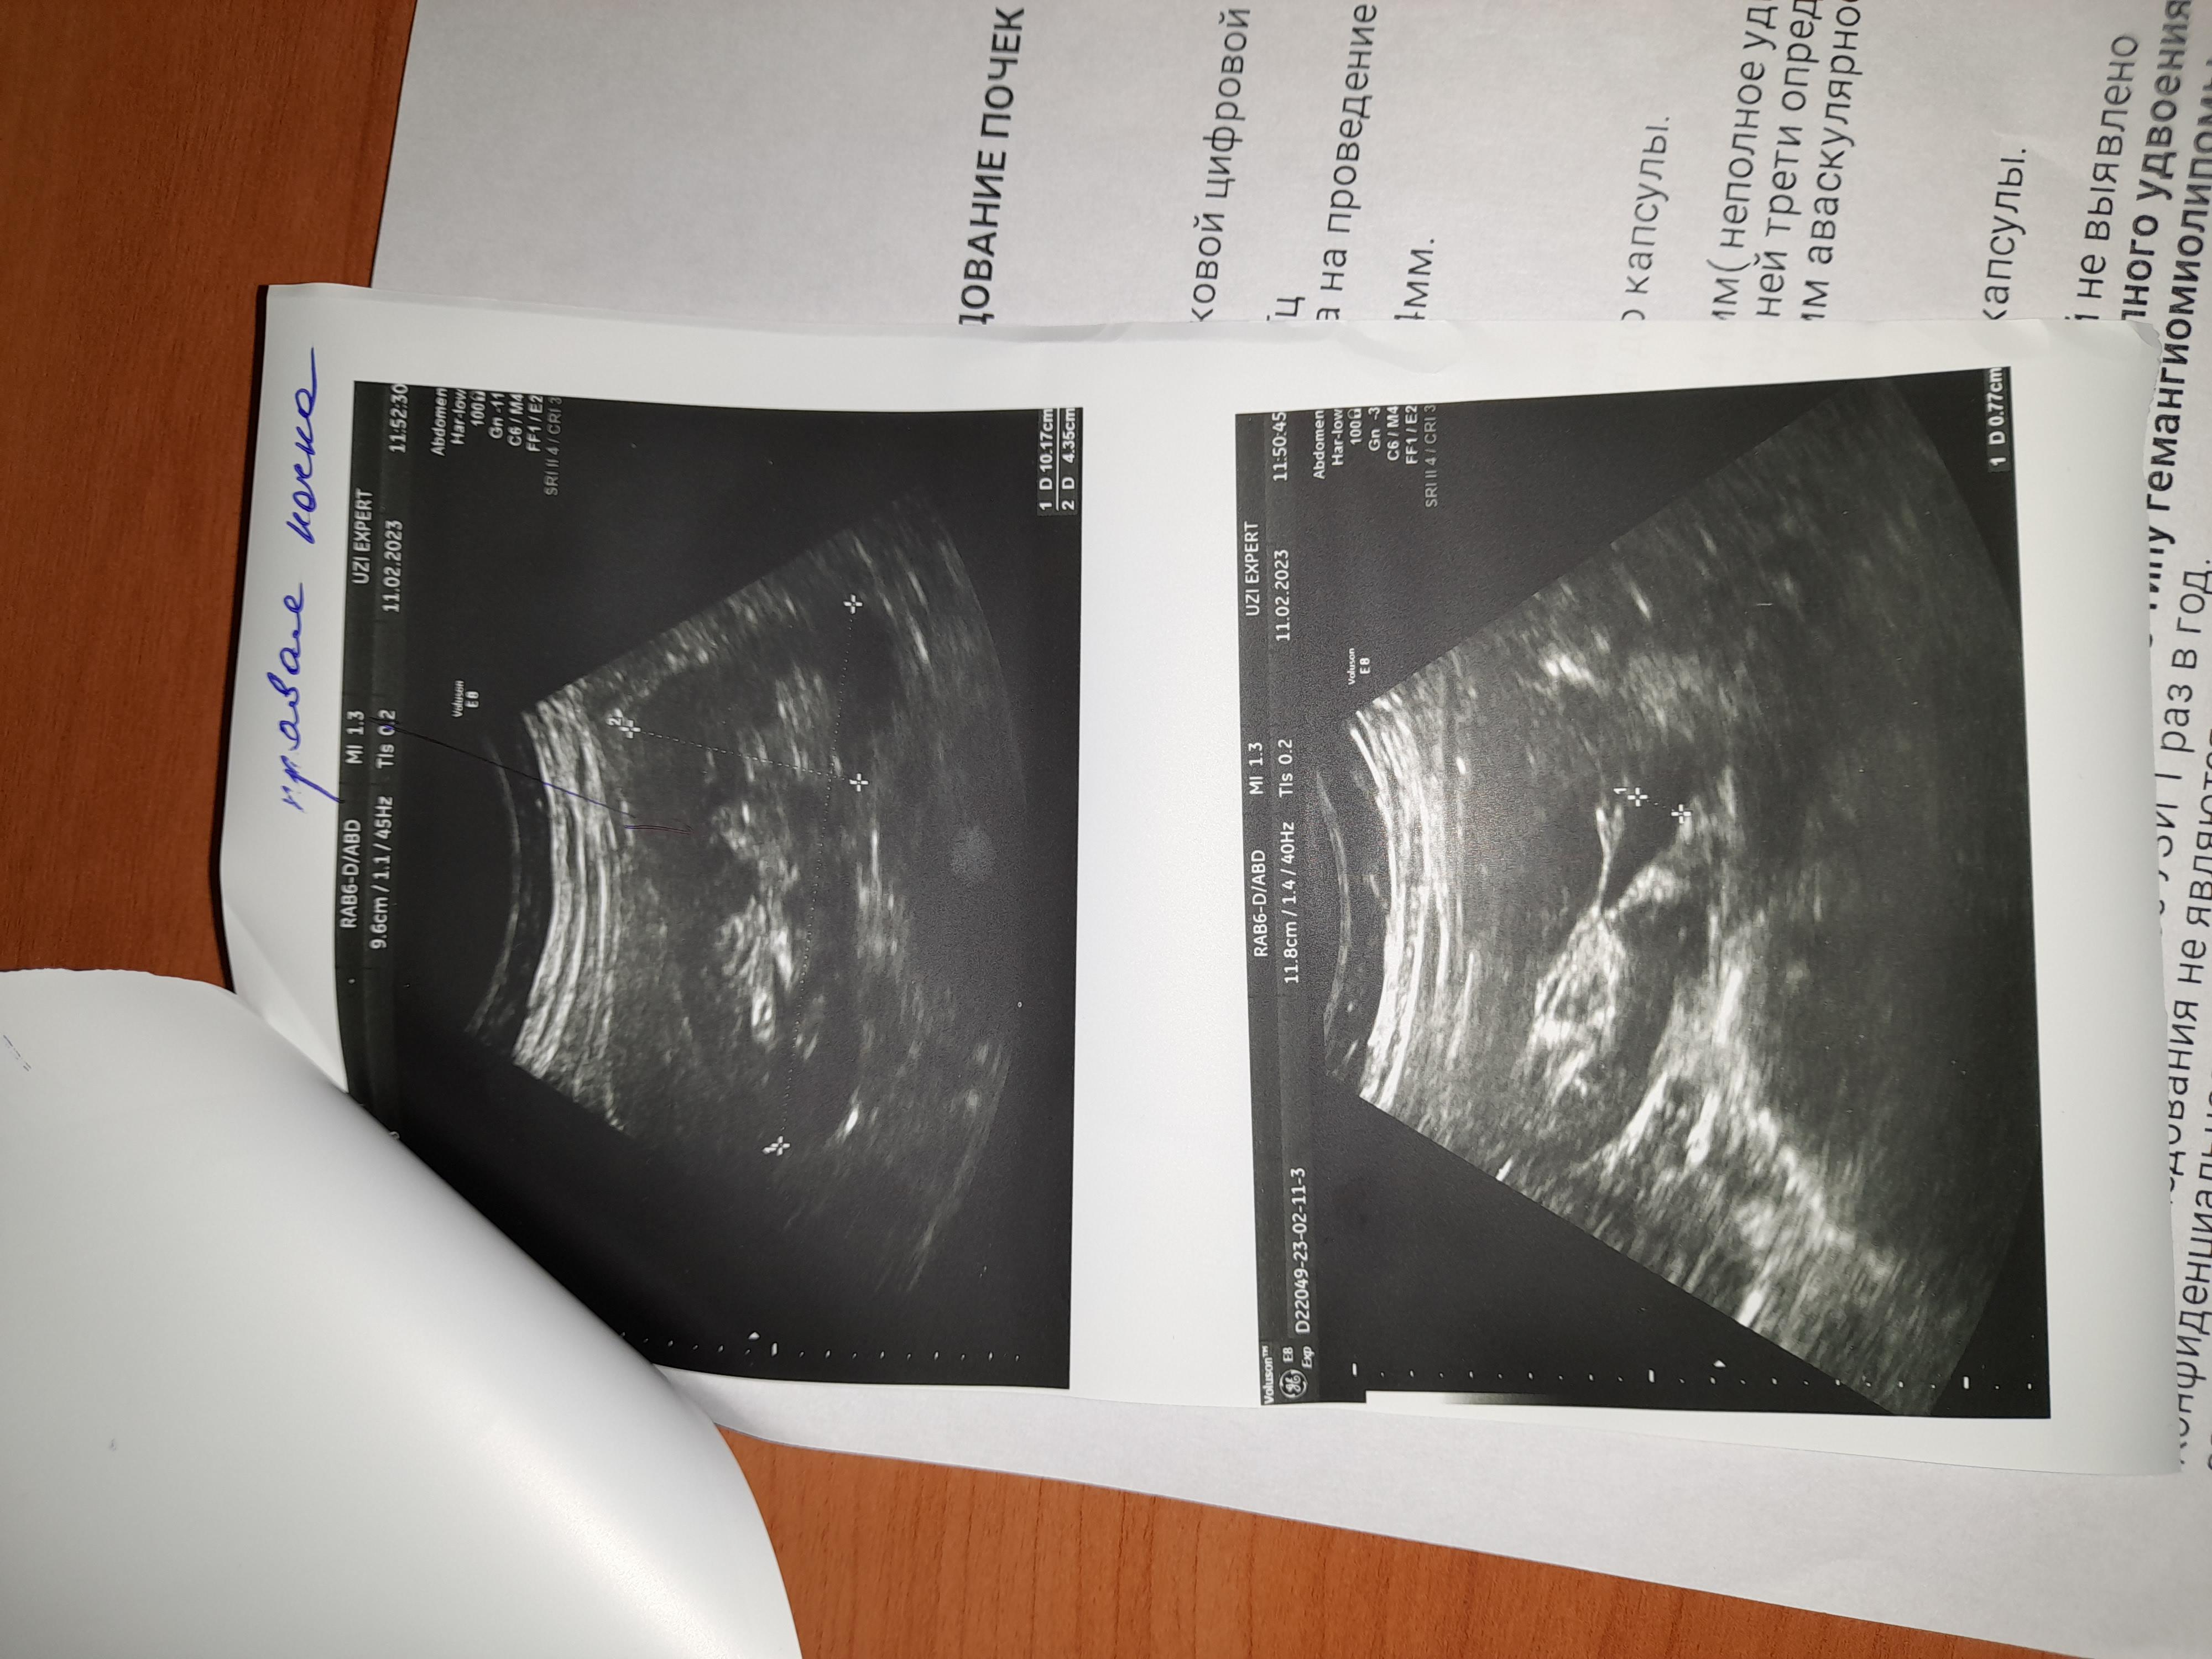

УЗИ почек, образование

Можно консультацию по УЗИ почек.

На сколько это серьёзно и опасно.

Добрый день! Для уточнения диагноза надо выполнить КТ почек с контрастированием. Далее - по ситуации. Удачи.